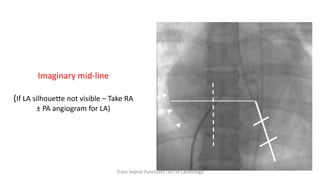

Imaginary mid-line

(If LA silhouette not visible – Take RA

± PA angiogram for LA)